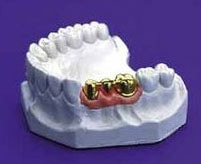

Brücken gehören zum langlebigen Zahnersatz. Material: Nichtedelmetall (Stahl), Edelmetall, Galvanotechnik, Vollkeramik, mit Keramik- oder Kunststoffverblendung.

Zahnlücken lassen sich mit einer Vollgussbrücke schließen. Die Nachbarzähne werden als Pfeiler überkront. Die Brücke wird aus hoch goldhaltigen, goldreduzierten oder Nichtedelmetalllegierungen gefertigt. Da vollkommen unverblendet, tragen Vollgusskronen und -brücken der Ästhetik in keiner Weise Rechnung. Da vom Gesetzgeber auch im sichtbaren Zahnbereich dieser festsitzende Zahnersatz vorgesehen ist, sollten Sie sich über die verschiedenen Möglichkeiten der Verblendung genauer informieren.